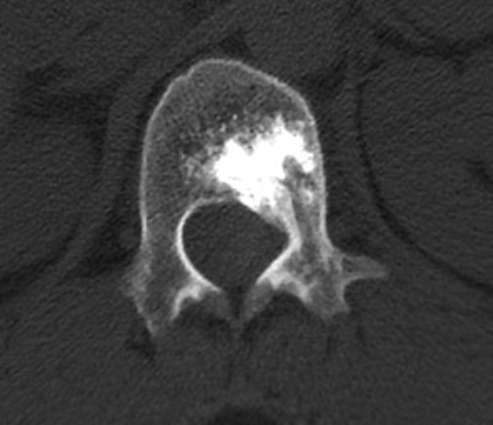

患者一、前列腺癌胸椎脊柱转移行骨水泥注射肿瘤灭活及镇痛术

患者因前列腺脊柱转移导致严重背部疼痛,行骨水泥注射后疼痛完全消失。